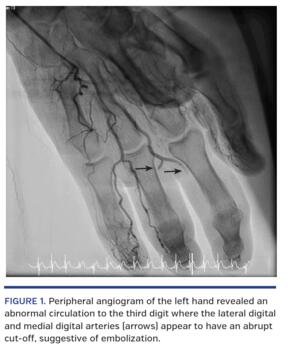

A 54-year-old male with a history of cigarette smoking and active intravenous drug abuse and multiple other comorbidities presented to the emergency department complaining of chest pain and left middle finger pain. He had electrocardiographic changes and positive cardiac troponins. An urgent cardiac catheterization showed severe coronary artery disease and poor ventricular function. Peripheral angiography of the left hand revealed an abnormal circulation to the third digit, where the lateral digital artery and medial digital artery appeared to have an abrupt cut off suggestive of embolization (Figure 1). Given the patient’s significant history of poor compliance, he was managed medically and discharged after vascular surgery evaluation. He later had an amputation of his left third digit.